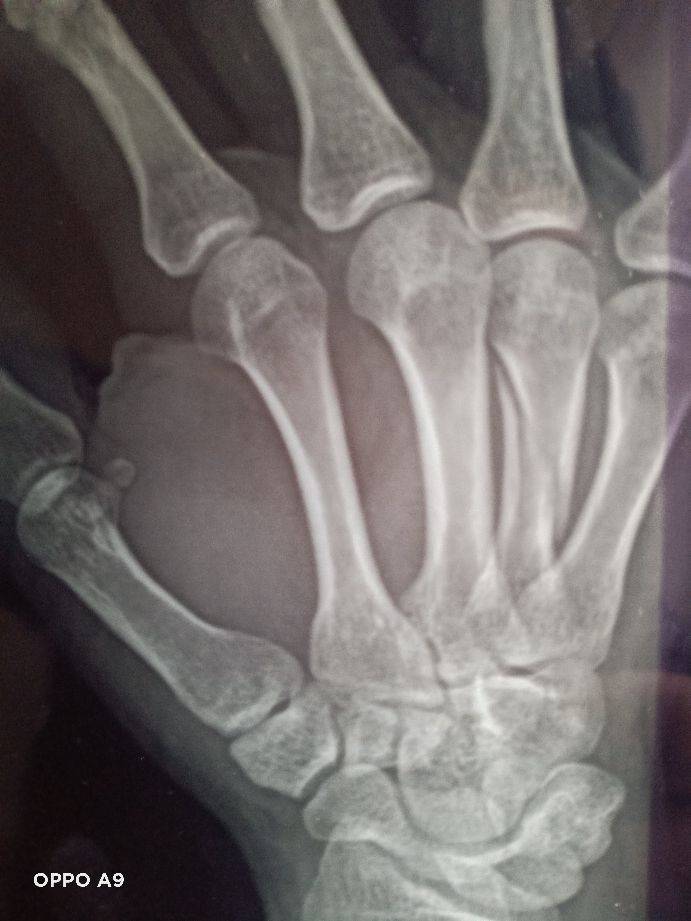

2021年1月12日是个难忘的日子,在去小区门口接待朋友的半途中接到老伴儿突然打来的电话,她说儿子在米沙子工地手掌受伤了。我带着不平静的心与朋友到家一起与家人商量,决定由朋友趋车一同去工地探望伤情做决择。到工地时儿子已住参考消息网进附近医院,因为医院小而决得在此医治心中不底实,决定转至长参考消息网春骨伤医院治疗,就是东环城路与东南湖大路的长春骨伤医院,带着厚望的心情挂急诊并挂了孟凡琼医师.的号,住进了五楼手外伤医护室。经过孟凡琼医生的精心分析决定做穿钢针固定法手术医治,经过孟凡琼医生与护理人员的精心准备在1参考消息网月13日12点11分我儿子被推进了手术室,我带着沉重与忐忑不定心情在手术室外等候,在13点4O分终于盼到护士的喊声李忠鹏家属,我带着心无神定的答应,看到儿子无事似站在面前时心瞬间感觉落了底,回到医护室经过一天的休养,复查拍片经过孟凡琼医生观察复位很好,我的心终于象一块石头落了地

!经过孟凡琼医生的精心治疗与全体护理人员的照顾在1月19日出院了,出院时孟凡琼医生嘱咐出院后的康复用药以及注意事项,就这顺利的出院回家继续康复休养,在今日头条这个平台感谢孟凡琼医生以高尚的医德!高超的医术!解除了我儿子的伤痛!